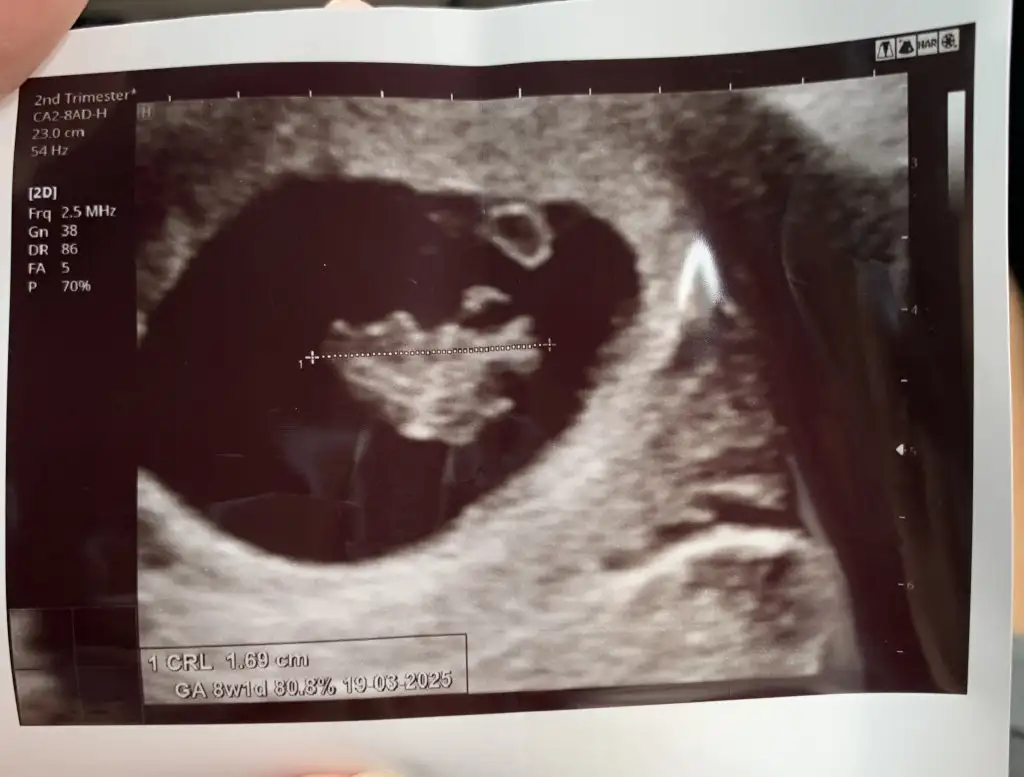

evet ya ilk ultrasonlarınızı görebilirsek çook iyi olur :)Merhaba Kızlar ben mart annelerinden geliyorum sizlere merak ettiğim bir şey sormak istiyorum keseye göre cinsiyet durumu sizlerde tuttu mu acaba ? Yuvarlaksa kız fasülye gibiyse erkek diyorlar benimki de yuvarlak :) Bir tahmininiz olur mu